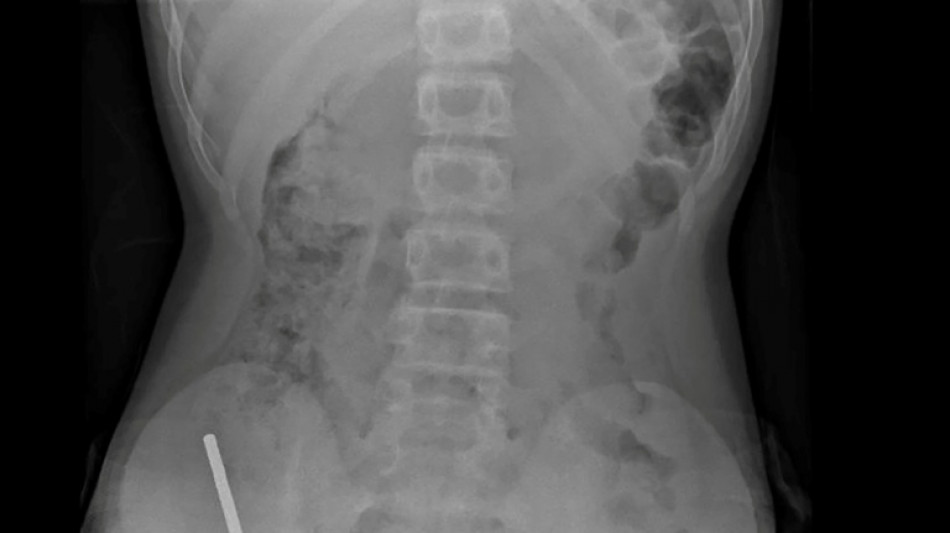

Bombay Durpun - Nouvelle-Zélande: un adolescent opéré après avoir ingéré près de 100 aimants achetés sur Temu